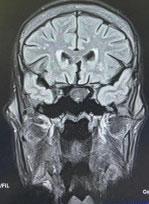

ANNs have been used in the clinical diagnosis, image analysis in radiology and histopathology, data inter- pretation in intensive care setting and waveform analysis.

ANNs have also been used in diagnosing cytological and histological specimens. PAPNET, a computerised automated screening system based on neural networks, has been developed to assist the cytologist in cervical screening and is one of the few ANN models which was promoted commercially .7 Breast,8 gastric, 9 thyroid,10 oral epithelial cells,11 urothelial cells,12 pleural and peritoneal effusion cytology 13 have all been subjected to analysis by neural networks with varying degree of success. In radiology, it is possible to use both human observations and direct digitised images as inputs to the networks. ANNs have been used to interpret plain radiographs,14 ultrasound,15 CT,16 MRI,17 and radioisotope scans18